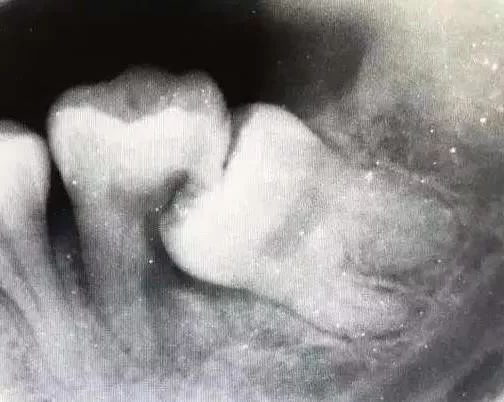

前倾阻生智齿,它的牙冠向前倾倒,直抵邻牙颈部,无论在口腔内还是X线片上都很直观,在形态上,跟警察跪压在黑人颈部非常相似,而且造成的后果也基本相同。

前倾智齿与邻牙形成一个敞开的间隙,经常会残留食物残渣,并且属于刷牙难以清理的死角,因此在邻牙邻面极易沉积菌斑,时间稍长即可形成邻面龋,龋损一旦攻破薄弱的牙骨质进入牙本质,邻牙即进入快速崩解毁灭期,于是产生临床上常见的“拔一送一”现象。

智齿顶坏了邻牙,一般都是因为疼痛剧烈而就诊,不是智齿痛而是邻牙痛,一般需要X线片进行确诊。临床根据邻牙龋损的深度,多半都是进行根管治疗或者拔除邻牙,但智齿本身大多是不治也不拔的,说实话,它真的像美国警察。

智齿顶着邻牙颈部的状况,是阻生智齿中产生危害最多的一种,临床上还有很多阻生智齿类型,前倾智齿冠部如果继续下倾,抵住牙颈部以下甚至牙根部位,乃至智齿全部埋伏在下颌骨内,那么产生危害不可预见,远不比肉眼可见的前倾智齿那么普遍。前倾智齿邻牙颈部菌斑导致龋坏是极大概率事件,而骨埋伏智齿只是可能形成“含牙囊肿”,或者因向前的生长潜力导致邻牙根破坏,它不存在菌斑因素,所以破坏没有那么直接,只能说风险客观存在,并且没有任何医生可以预测。